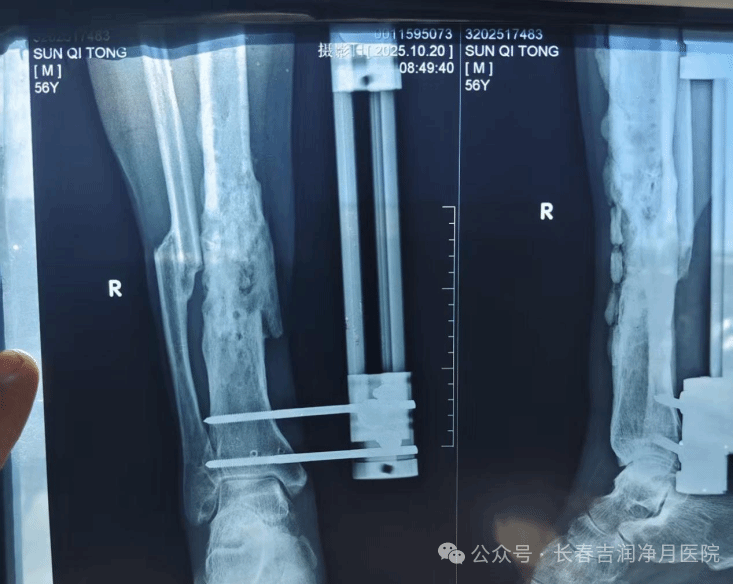

2025年10月,张先生入住我院接受决定性治疗。于铁成主任团队经过充分准备,为患者实施第二阶段手术。术中通过精准操作,完整取出抗生素链珠,彻底清创后植入抗生素硫酸钙骨粉。手术过程顺利,耗时短,创伤小。

(2025年10月,第二次手术术中胫腓骨正侧位)